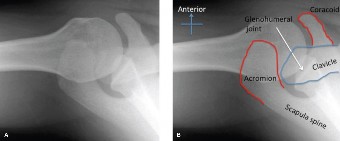

Radiographic Evaluation

Immediate post-reduction radiographs were obtained to confirm concentric reduction and evaluate for osseous pathology. The standard trauma series included a true anteroposterior Grashey view, a scapular Y view, and an axillary lateral view.

The Grashey view confirmed concentric reduction of the glenohumeral joint with no evidence of superior migration of the humeral head, suggesting an intact rotator cuff. However, close inspection of the anteroinferior glenoid rim revealed a distinct sclerotic line and a small, displaced osseous fragment, pathognomonic for a bony Bankart lesion. Furthermore, an internal rotation anteroposterior view demonstrated a dense vertical line in the superolateral aspect of the humeral head, representing a Hill-Sachs impaction fracture. The axillary lateral view corroborated the presence of the anterior glenoid rim fracture, showing a deficiency in the normal pear-shaped contour of the inferior glenoid.